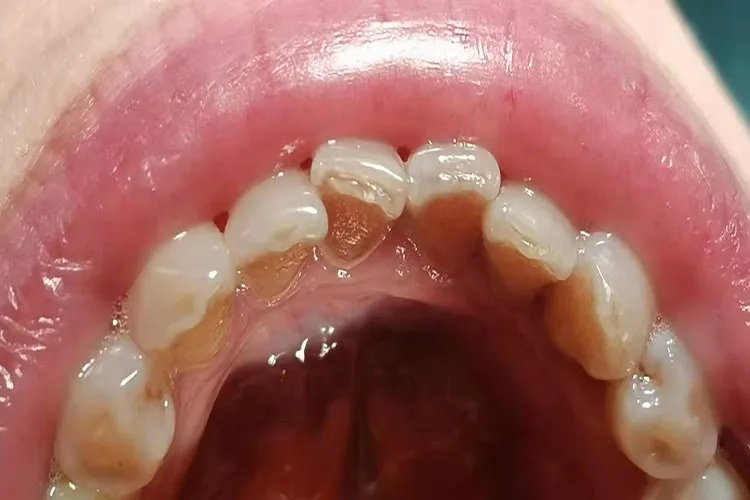

牙结石龈上牙结石常沉积在牙冠,直接可看到的牙结石称为龈上牙结石,呈黄或白色,一般体积较大,尤其是在与唾液腺导管开口相应处的牙面上沉积更多,如上颌第一磨牙颊面和下颌前牙的舌面。

龈下牙结石多在龈缘以下,肉眼看不到,在X线片上可见。呈褐色或黑色,较龈上牙结石体积小而硬,一般与牙面的附着比龈上牙结石更牢固。